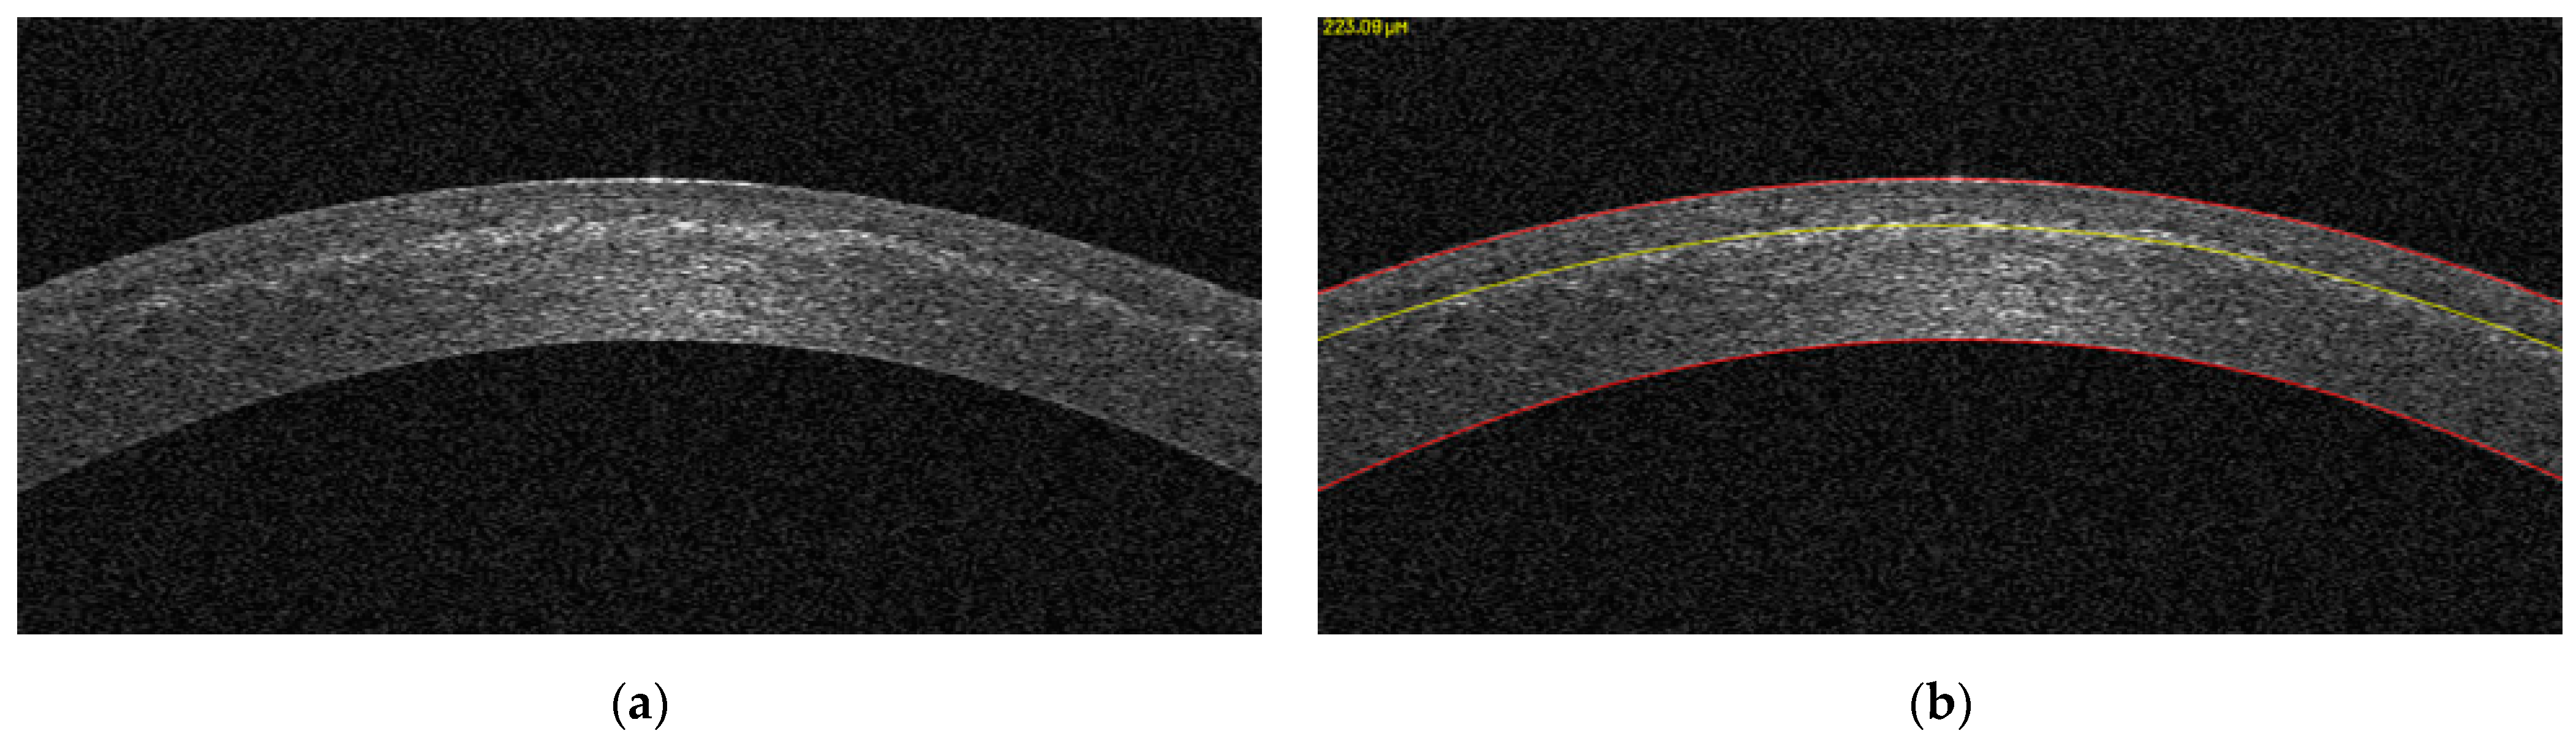

2.3. Analysis of Demarcation Line Depth